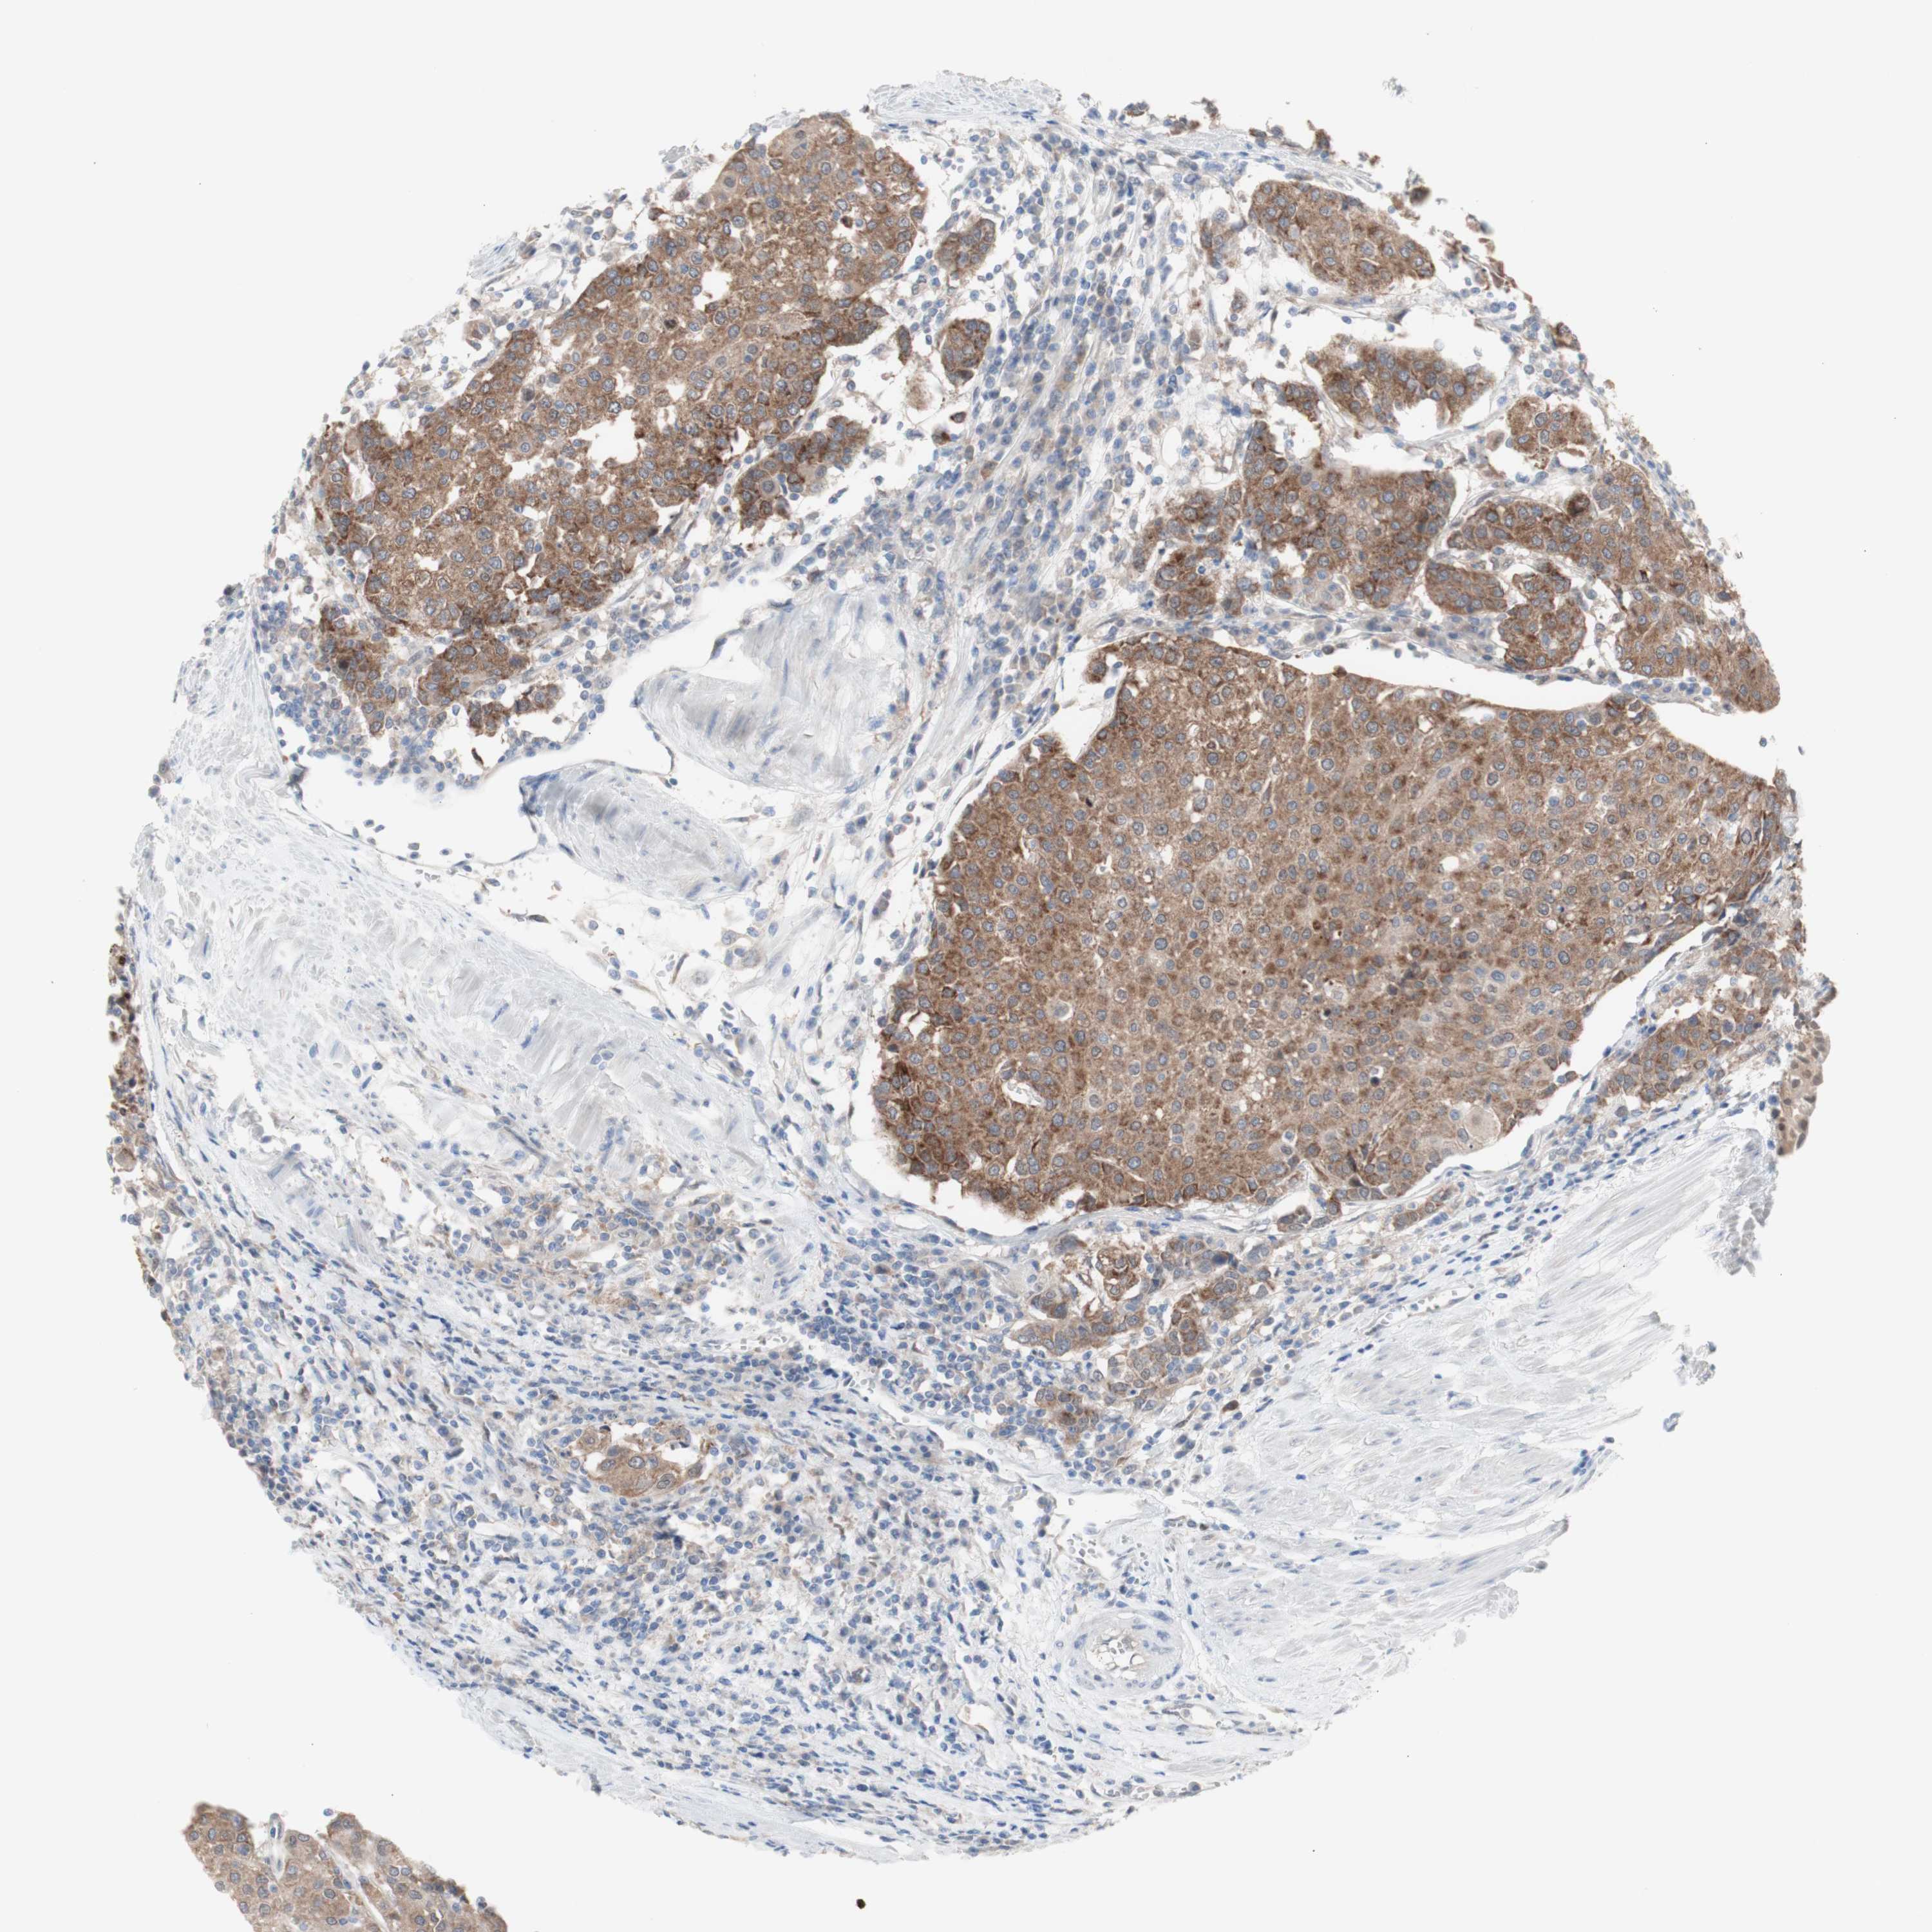

UROTHELIAL CANCER - Protein expressioni

A mouse-over function shows sample information and annotation data. Click on an image to view it in a full screen mode. Samples can be filtered based on level of antibody staining by selecting one or several of the following categories: high, medium, low and not detected. The assay and annotation is described here.

Note that samples used for immunohistochemistry by the Human Protein Atlas do not correspond to samples in the TCGA dataset.

Antibody stainingi

Antibody staining in the annotated cell types in the current human tissue is reported as not detected, low, medium, or high, based on conventional immunohistochemistry profiling in selected tissues. This score is based on the combination of the staining intensity and fraction of stained cells.

Each image is clickable and will lead to virtual microscopy that enables deeper exploration of all samples and also displays staining intensity scores, fraction scores and subcellular localization as well as patient and tissue information for each sample.

Antibody HPA005525

Antibody HPA064708

Antibody CAB012459

Staining

High

Medium

Low

Not detected

Intensity

Strong

Moderate

Weak

Negative

Quantity

>75%

75%-25%

<25%

None

Location

Nuclear

Cytoplasmic/membranous

Cytoplasmic/membranous,nuclear

Urothelial carcinoma, High grade

Urothelial carcinoma, Low grade

Urothelial carcinoma, NOS